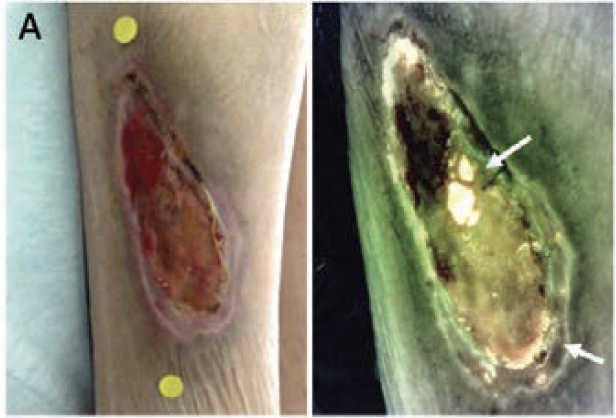

The presence of red fluorescence in the image is indicative of bacterial loads of greater than 104 CFU/g, and cyan fluorescence is indicative of the presence of Pseudomonas aeruginosa.11,17-19 This is distinct from wound tissue fluorescence signals, which appear as shades of green (ie, skin, slough) and dark maroon (ie, blood or granulation tissue). Figure 1 provides examples of wounds from this study with either red or cyan fluorescence that indicates the presence of bacteria at those loads.

After obtaining the fluorescence images, the clinician examined and interpreted them. The presence of red or cyan fluorescence was indicative of elevated bacterial loads based on the extensive research done on the technology; thus, microbiologic analysis was not performed to confirm the bacterial presence in this study.